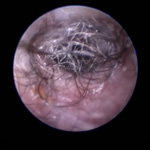

角化症、脂漏症という生まれつきの体質を持ったワンちゃんは耳垢が多くなりがちです。また、角化症、脂漏症の長毛種となれば、耳の中に毛が生えた犬種も多く耳道から耳垢を排泄しにくくなります。それらが原因で耳に汚れがたまります。また長毛種はトリミングに行く回数も多く、耳を洗う機会が多くなります。こんな負の連鎖があり、いずれも耳を悪くする大きな原因になります。その全ての要因に対処しなければ耳の病気は解決しません。写真は鼓膜手前に耳垢や毛が蓄積し、通常の耳洗浄ではきれいにできない状態です。セカンドオピニオンで来院されるワンちゃんで最も多い病気の1つです。

フレンチブルドックはアトピー性皮膚炎、食物アレルギー、脂漏症、甲状腺機能低下症など皮膚病になりやすい犬種です。さらにフレンチブルドックの耳道はもともと入口がとても広く、鼓膜手前で極端に狭くなっています。もし、これらの皮膚病を発症すると外耳炎が起こりやすくなります。外耳炎が起こると耳垢が溜まり、耳洗浄による耳道刺激があったり、微生物の増殖など負のサイクルに陥ることがあります。さらに耳道周囲の体毛が耳の中に入りやすいため、鼓膜手前に毛が蓄積します(写真)。体毛、微生物が増殖した耳垢、皮膚病の放置といった悪化因子が重なると非常に重度の中耳炎になります。